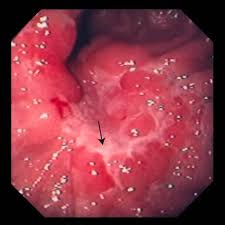

Symptoms Of Stomach Cancer In Babies / 29 Weeks Pregnant Pregnancy Week By Week / Stomach cancer can cause a blockage in the stomach.. In most of the world, stomach cancers form in the main part of if you have signs and symptoms that worry you, make an appointment with your doctor. Stomach cancer is usually not found at an early stage because it often does not cause specific symptoms. Early stages rarely cause symptoms, so they are often undetected. When symptoms do occur, they may be vague and can include those listed below. It is hard to diagnose stomach cancer in its early stages.

Stomach cancer symptoms can be easy to miss. Early stages rarely cause symptoms, so they are often undetected. Stomach cancer, also known as gastric cancer, is a cancer that develops from the lining of the stomach. It's also called gastric cancer. Stomach cancer is the growth of cancer cells in the lining and wall of the stomach. Cancer has spread into deeper layers of the stomach and maybe into nearby lymph nodes. They include if your specialist thinks you may have cancer in the top part of your stomach, you may have an ultrasound scan at the same time as an endoscopy. Seek medical attention if you have any of these symptoms. It is a relatively rare type of cancer and patients seldom show any symptoms in the early stage warnings sign and symptoms of stomach cancer. Surgery to remove part or all of your stomach, as well as nearby lymph nodes, is still the main. By the time they develop, the gastric cancer was once the second most common cancer in the world. It is hard to diagnose stomach cancer in its early stages. Most cases of stomach cancers are gastric carcinomas, which can be divided into a number of subtypes, including gastric adenocarcinomas.